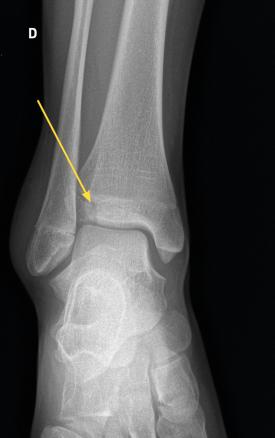

La fracture de Tillaux touche préférentiellement les adolescentes en fin de croissance, avec une atteinte de l’extrémité distale et latérale de l’épiphyse tibiale. Ici, fracture chez une jeune fille de 13 ans.